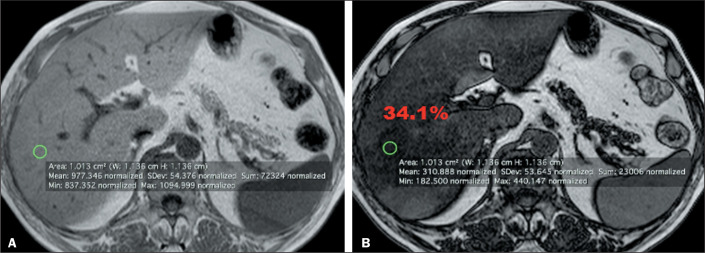

目的评估量化肝脂肪变性的三种不同测量策略,并研究同质性和异质性肝脂肪变性之间的差异:通过磁共振成像检查进行回顾性研究。我们在两个匹配组:同质性和异质性脂肪变性中评估了量化肝脂肪变性的三种不同策略。在所有测试中,我们都将 P < 0.05 视为显著性水平:结果:在异质性脂肪变性组中,用 1 平方厘米的感兴趣区(ROI)来测量改变最严重区域的信号强度的策略在量化上有显著差异,而轴切片中四个 1 平方厘米感兴趣区或代表性目标区域的平均值没有显著差异。在弥漫性肝脂肪变性中,所使用的任何策略都没有明显差异。类内相关系数介于 0.96 和 0.99 之间,95% 置信区间为 0.93-0.99:仅使用一个 ROI 进行磁共振成像脂肪肝量化的代表性较差,尤其是在异质性脂肪肝中。四个 ROI 的平均值策略与实质组织代表性分割区域策略之间没有明显差异。

Results: In heterogeneous steatosis group, the strategy with a region of interest (ROI) of 1 cm2 to measure the signal intensity in the most altered area showed significant variations in the quantification, while the average of four ROIs of 1 cm2 or representative target area in axial section did not vary significant. In diffuse hepatic steatosis, any strategy used showed no significant difference. The intraclass correlation coefficient ranged between 0.96 and 0.99, with 95% confidence interval of 0.93-0.99.

Conclusion: The quantification of fat liver by magnetic resonance imaging using only one ROI is less representative, especially in heterogeneous steatosis. There was no significant difference between the average of four ROIs strategy and the strategy of representative segmentation area of parenchyma.